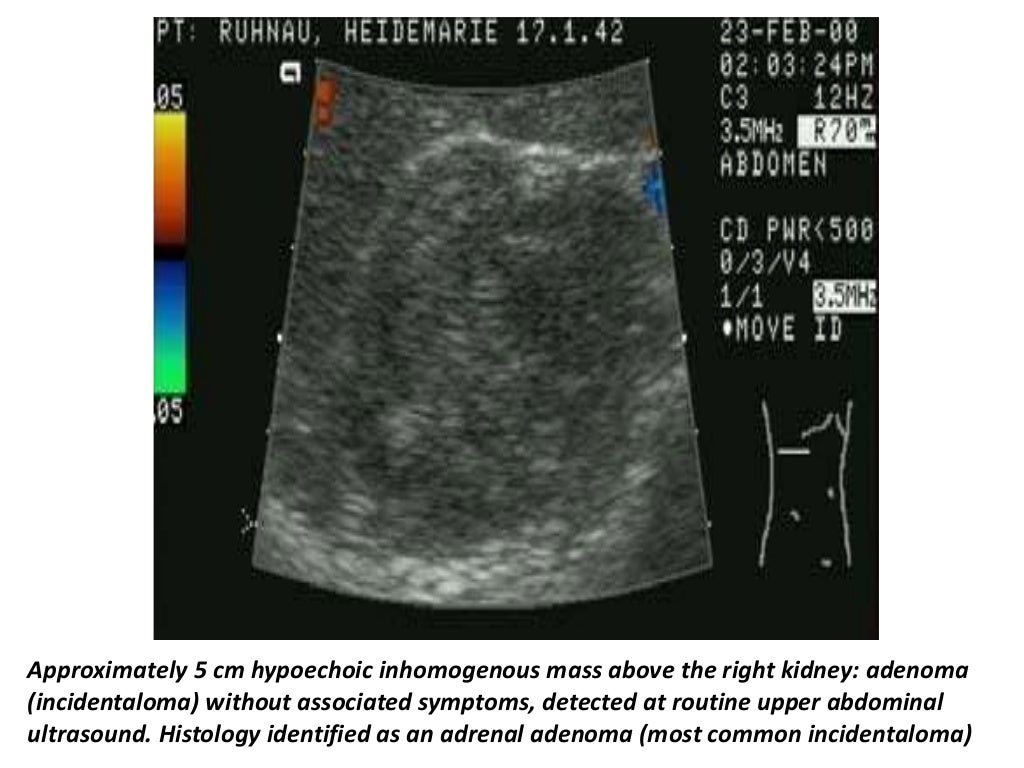

Ultrasound image showing enlarged hypoechoic adrenal gland. Pyramidal Adrenal Gland Ultrasound Preparation adrenal glands ultrasound patient prep: the left adrenal gland is imaged by a posterolateral approach in coronal plane through the long axis of the. Perform a real time survey of the adrenal glands. Any lesion growth is suspicious for malignant disease (fig. Scan technique, patient positioning and anatomic consideration for adrenal sonography. in this article, we discuss. Adrenal Gland Ultrasound Preparation.